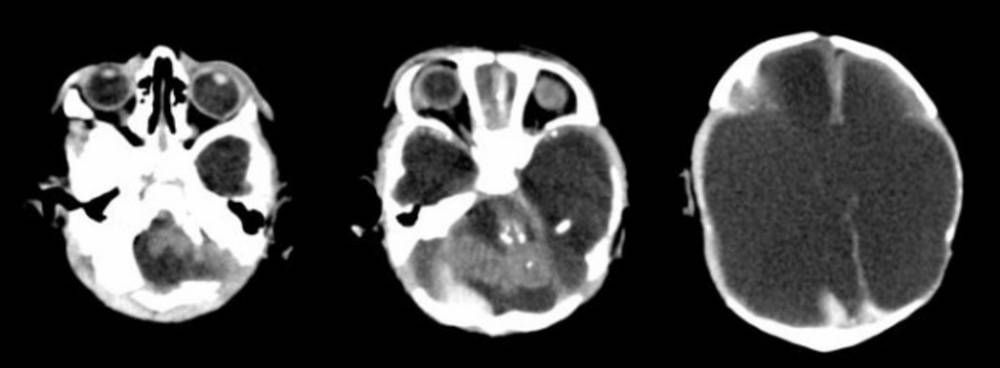

El Ministerio de Salud de Santa Fe informó que fue detectado el primer caso en la provincia de un bebé nacido con microcefalia por efecto del zika y destacó que la madre contrajo la enfermedad en este territorio.

El director de Epidemiología de la cartera de Salud santafesina, Julio Befani, precisó que se trata de un niño que "nació en 2016", pero "recién en la segunda semana de 2017 terminaron los estudios en el Instituto Maiztegui" que confirmaron el cuadro. "Con los datos que nos enviaron ellos, más los registrados de las malformaciones congénitas estamos en condiciones de concluir que el caso de microcefalia fue consecuencia del contagio de zika de la madre del niño", sostuvo el funcionario, en declaraciones a la prensa.